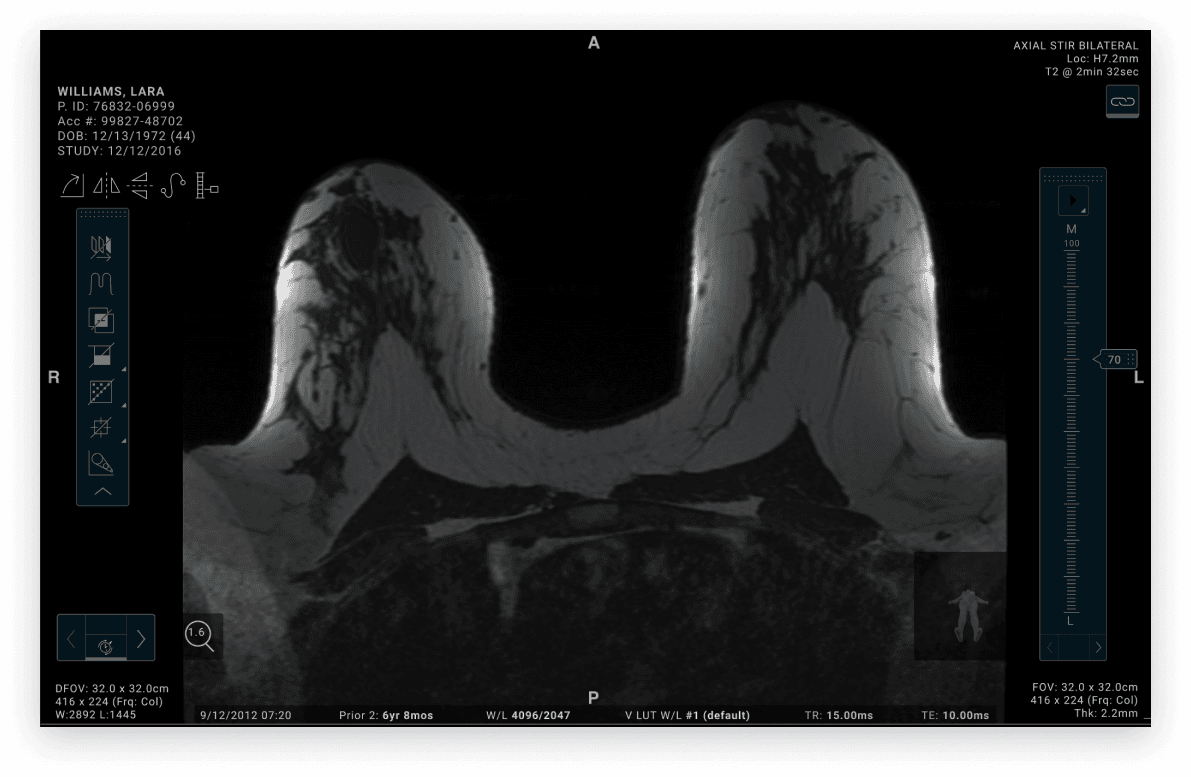

(*patent pending) Hologic’s MRI workstation is used by radiologists to review and interpret breast imaging studies during diagnostic evaluation. As Co-Design Lead, I partnered with cross-functional teams throughout the product lifecycle to gather user needs, define workflow requirements, and develop concepts that supported efficient image analysis in a high-stakes clinical environment.

For the purpose of this case study, we will focus on MRI workflows.

To support radiologists working in low-light reading environments, the final interface was designed to maintain sufficient contrast between imaging studies, overlays, and diagnostic tools — while minimizing visual strain during prolonged interpretation sessions.

The in-view toolbar allowed clinicians to access commonly used tools without interrupting their review flow, supporting more efficient annotation and comparison across imaging studies.